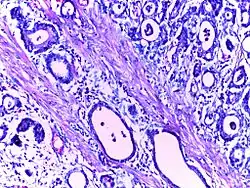

![]() | Cystic hyperplasia of endometrium | Micrograph showing cystic hyperplasia of endometrium. Cystically dialated glands are lined by proliferative type of epithelium. Stroma also resembles proliferative phase. No atypia is seen in the cells. | Category: Histopathology of hyperplasia endometrium | Cystic hyperplasia |